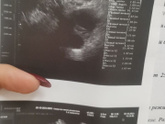

Прошла второй скрининг и расстроилась

Приклеплю фото. Узист смотрел меня минут 40, Крутил то на левый то на правый бок, смотрел кровотоки. Итого плохой кровоток в пуповине. Развитие ребёнка … Читать далее